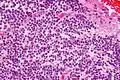

Tumor samples stained using H&E stain and examined under the microscope revealed that CNC is a well-differentiated tumor with benign histological features. The tumor is composed of “uniform, small-to-medium-sized cells with rounded nuclei, finely stippled chromatin and inconspicuous nucleoli, along with scant cytoplasm.” CNC are characterized by perivascular pseudorosettes, circular/flower-like arrangements of cells with a small blood vessel at the centre, and polygonal small cells with a clear perinuclear halo, sometimes called the ‘fried egg’ appearance, and is clear or slightly eosinophilic. The main histomorphologic differential diagnosis is oligodendroglioma. While the tumor cells are dense in some areas, areas with anuclear, less dense tumor parts were dispersed throughout. The anuclear areas may have a fine fibrillary matrix, like that of neuropil regions. Long, thin-walled, capillary-sized vessels represent the vascularity of CNC. These vessels are arranged in a linear branching pattern, with an endocrine appearance. Thin-walled dilated vascular channels, as well as foci of calcification, were readily identified in many cases.[4]

Very high mag.

Very high mag. High mag.

High mag. Very high mag.

Very high mag.